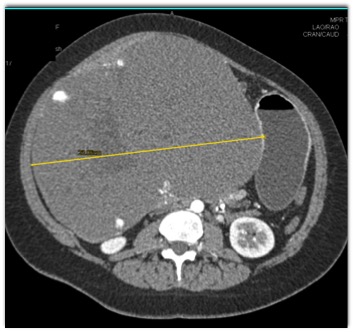

The best diagnosis for this hepatic mass is?

hepatoma

cholangiocarcinoma

hemangioma

FNH